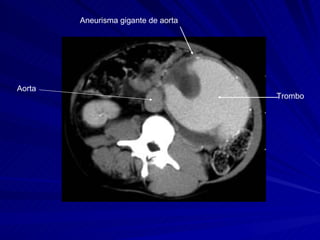

Aneurisma gigante de aorta Trombo Aorta

Aneurisma gigante deaorta Trombo Aorta